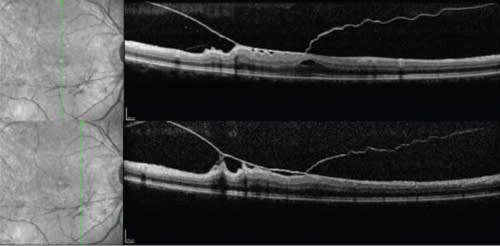

Use of raster scans. Focal areas of VMAs can be missed by standard horizontal and vertical scans through the fovea. Raster scanning patterns help to diagnose and determine the extent of the VMAs to plan for vitreoretinal surgery. One can perform a maximum of 651 scans at 11 µm apart, from arcade to arcade, to delineate the full ana tomy of the macula in relationship to the vitreous. Figures 2 and 3 show the various patterns of vitreomacular tractions in the same eye. Preoperative knowledge of these adhesions helps to plan the intraoperative steps.

Figure 2. Horizontal raster SD-OCT scans in an eye with vitreomacular traction.

Top: scan through fovea showing a lamellar hole and posterior hyaloid with attachment nasally causing retinal traction.

Middle: Scan below the fovea showing attachment of posterior hyaloid with increased retinal thickness.

Bottom: Scan below the fovea showing posterior hyaloid with retinal traction causing plication (areas of loose adhesions between posterior hyaloid and retina). Raster scans give important information about the extent of traction and are helpful in surgical planning.

Figure 3. Vertical raster SD-OCT scans of the same eye as in Figure 2 showing posterior hyaloid causing vitreomacular traction with plication. Area of haze above and below the posterior hyaloid is artifact and does not represent vitreous gel.